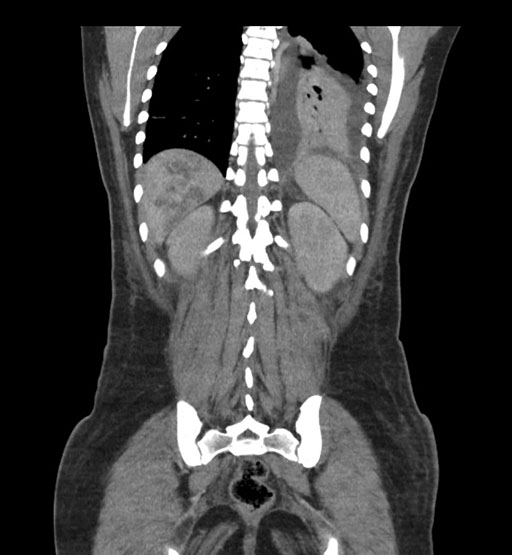

Coronal Arterial

Coronal Venous